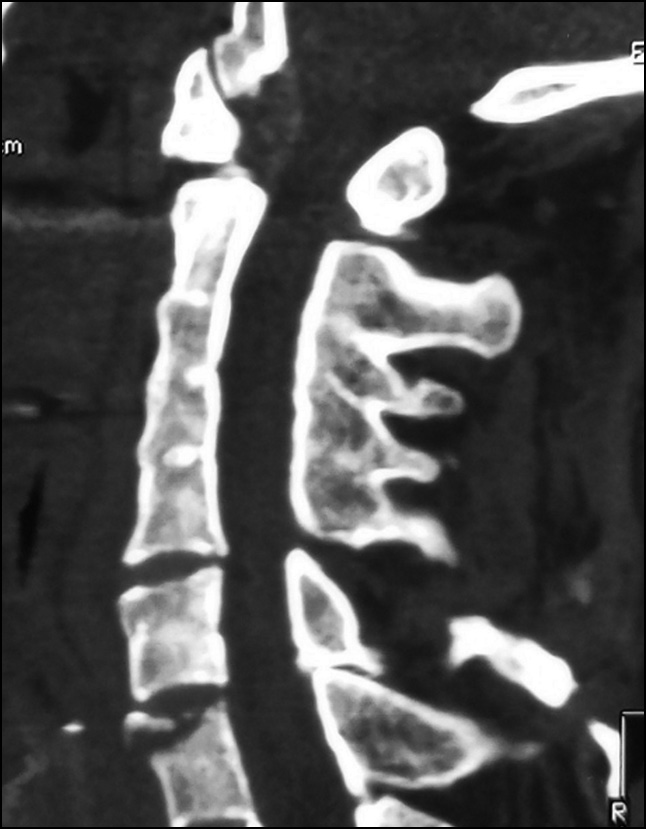

Control radiographs revealed multiple heterotopic ossifications of the axial and peripheral skeleton and submandibular region and multiplanar spinal deformity (Figs. 1–3). Computed tomography revealed synostosis of the 2nd–5th cervical vertebrae, which exhibited fusion of not only their posterior elements but also their bodies (Figs. 4 and 5). Synovial chondromatosis, one of the most common manifestations of FOP, was identified during a hip joint examination (Fig. 6). In addition to intra-articular chondromal bodies, heterotopic ossifications in the hip joints completely inhibit the movements in this skeletal region and significantly impeded walking (Figs. 7 and 8).

Fig. 4. CT scan of the cervical spine, sagittal view: synostosis of the bodies and posterior elements of the C2-C5 vertebrae, heterotopic ossifications of the neck muscles.